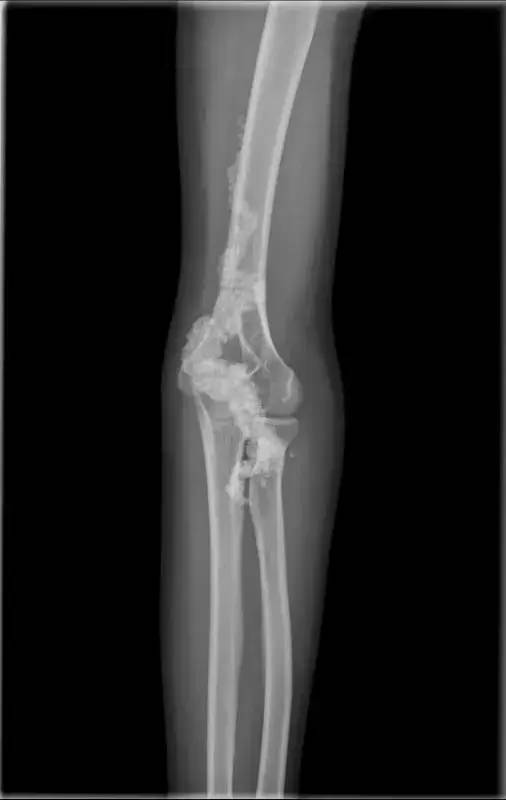

龙蟠柱样改变 (是曹来宾教授首先提出这一征象),符合钙质沉着症。

龙蟠柱样改变为钙质沉着症较特异征象,钙化沿血管周围旋转如中国建筑特有的龙蟠柱样,邻近骨关节一般没有改变。